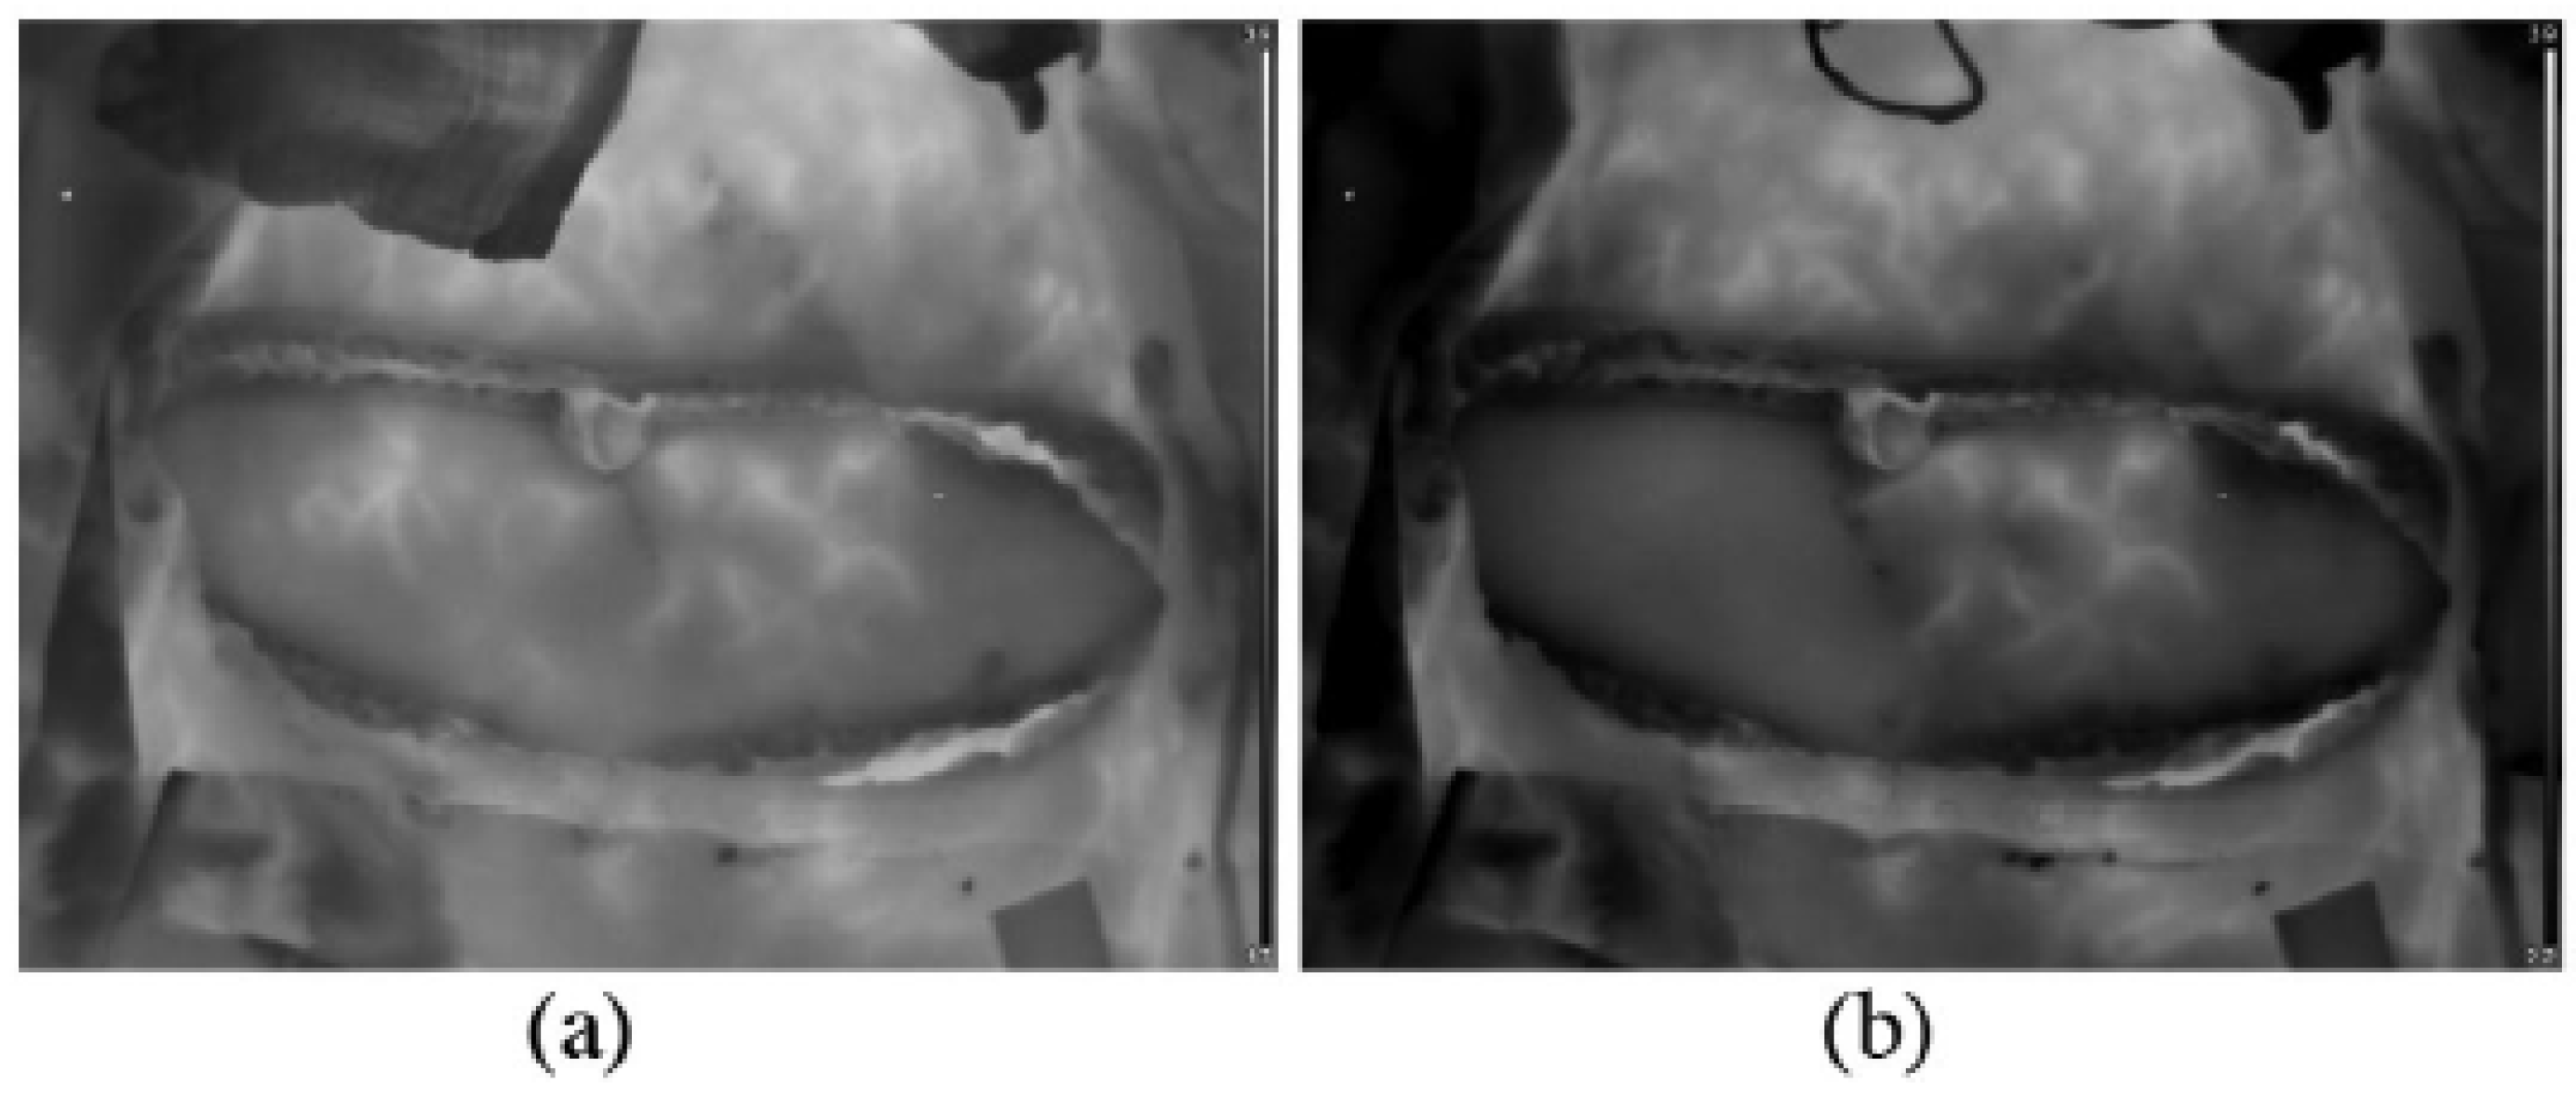

1.1.1. DIEP Flap Breast Reconstruction

1.2.1. DIEP Flap Breast Reconstruction

2.1. DIEP Flap Breast Reconstruction